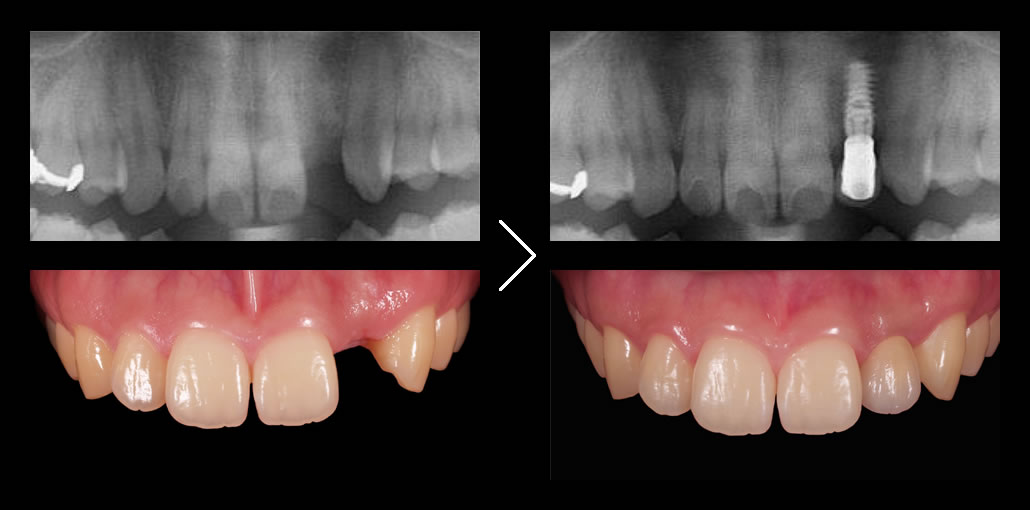

なぜ、前歯のインプラントが難しいのか

- 上の前歯はもともと骨が薄い

- 歯を失うと大きく骨が吸収してしまう

- 治療後に歯ぐきも下がりやすい

そのため、 骨が残っているところに無計画にインプラントを埋入するケースがほとんどで、その結果インプラントの上部構造の形態に無理が生じたり、見た目の酷い治療結果となりがちです。